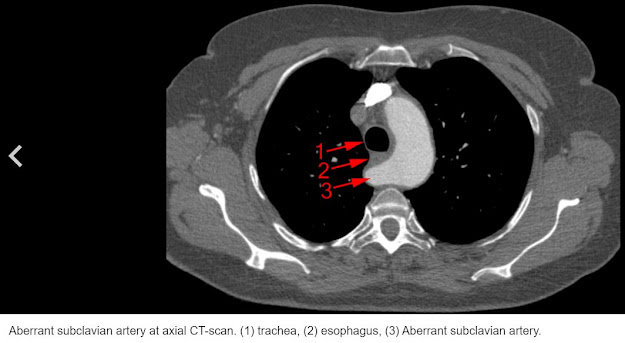

The CT scan also detected a variance in my right clavicle artery.

A right retroesophageal subclavian artery (RRESA) is a rare anatomical variant. It's a result of failure in the congenital development of the primordial aortic arch. The anatomic and morphologic variations of the aortic arch and its branches are significant for diagnostic and surgical procedures in the neck.

The doctors asked me if I ever had trouble swallowing or shortness of breath. I've always had trouble swallowing potatoes, but I thought that was normal for everyone to feel like food got stuck in their esophagus. Guess not. In regards to breathing, I was told I had exercise-induced asthma when I was young. My albuterol inhaler never seemed to work though if I had an "asthma attack" while running. Could this aberrant artery be the actual reason?